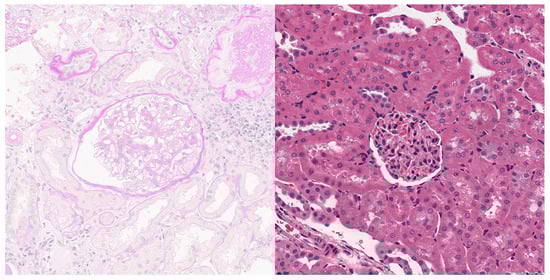

Concerning the learning performance of the model, each image in the dataset was carefully categorized by pathologists to ensure the accuracy of the training data. Figure 3 shows image patches containing human and mouse glomerulus processed from the original WSIs. The left and right images are from a patient with IgA and a mouse, respectively.

Figure 3. WSI patches containing human (left) and mouse (right) glomerulus.